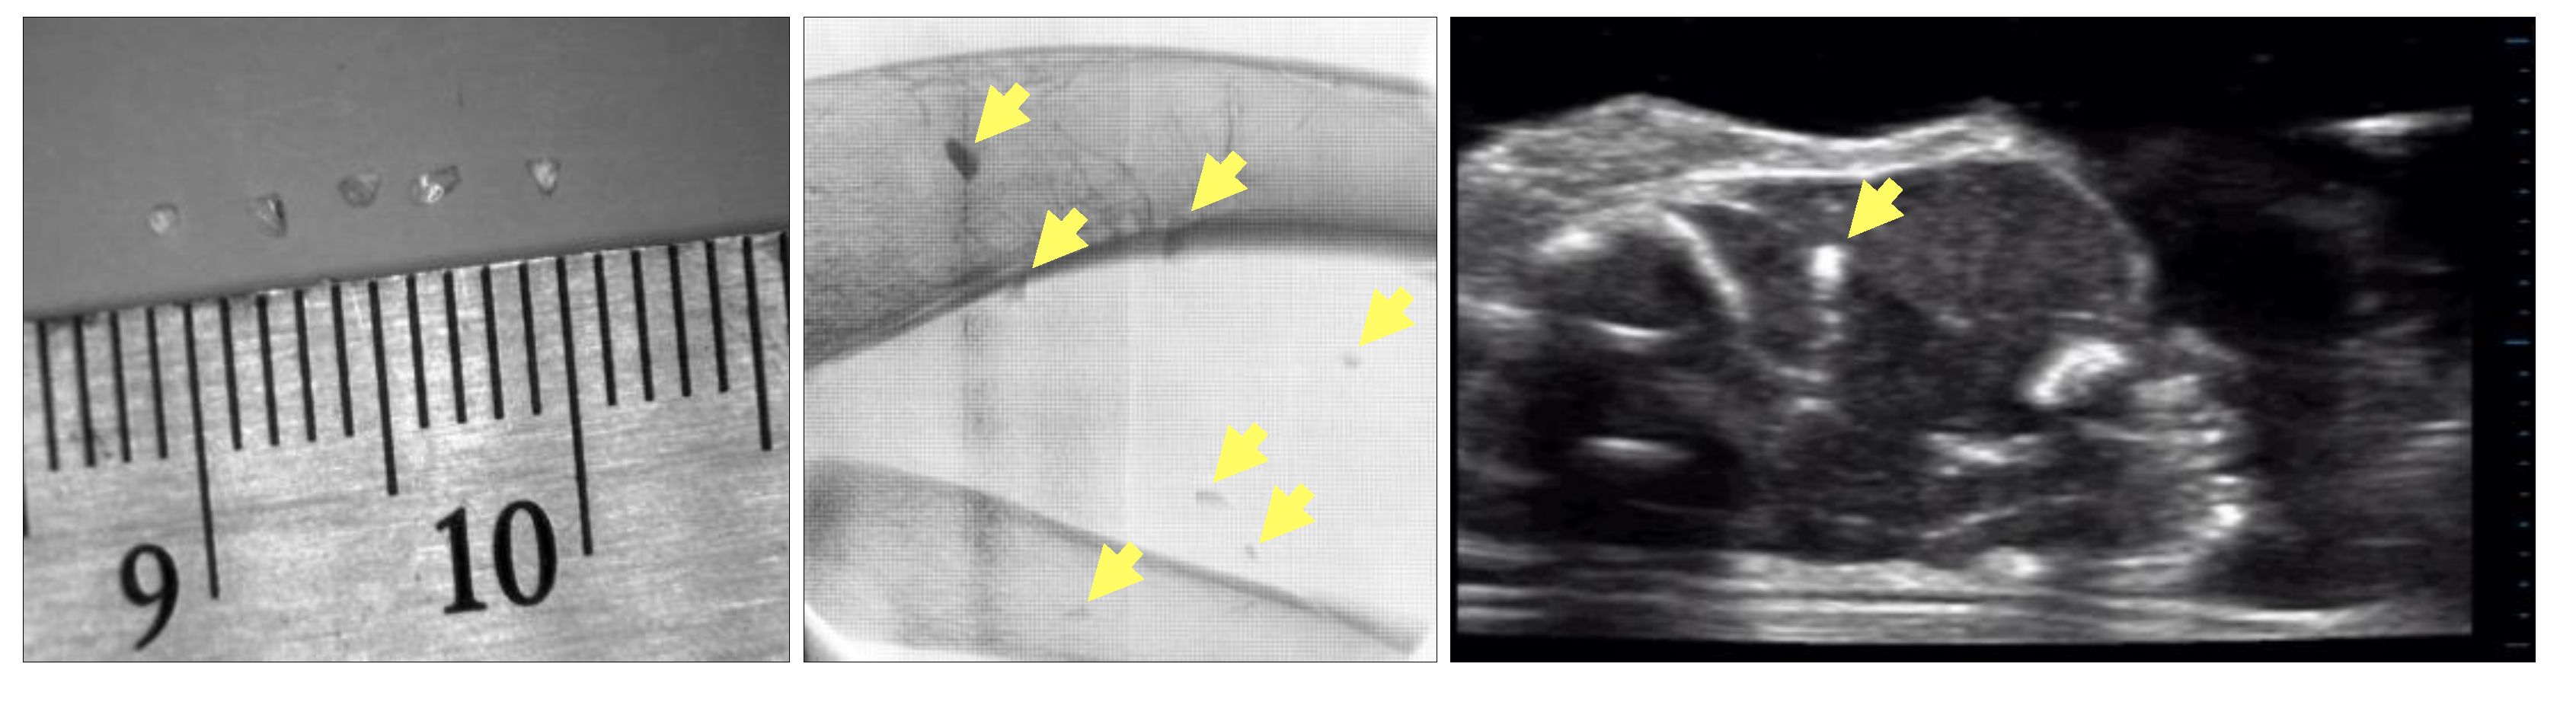

Figure 8 from Digital Radiography (DR) vs Computed Radiography (CR

Figure 8 from Digital Radiography (DR) vs Computed Radiography (CR Radiography Vs Ut Computed radiography (cr) uses a storage phosphor imaging plate in place of the film; Find out how to choose the best. Find out how to choose the best method for. Learn about the benefits and drawbacks of five common methods for inspecting welds: Radiography, magnetic particle, liquid penetrant, ultrasonic and visual. Learn how to use magnetic particle test (mt) and. Radiography Vs Ut.